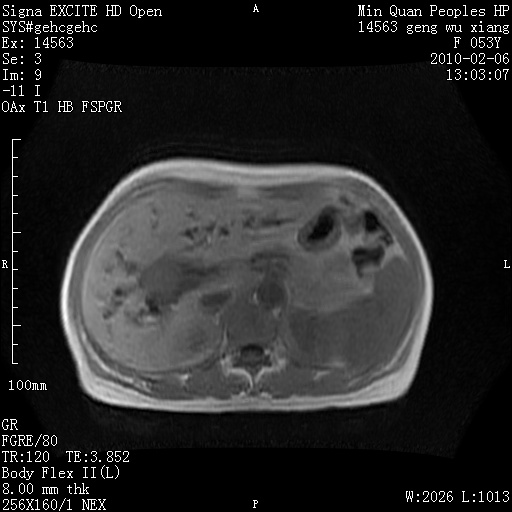

标题: MRI2762:胆道梗阻原因?

f,53y,全身黄染多日。

高位胆道梗阻 胆管癌可能性大

支持 高位胆道梗阻 胆管癌可能性大。